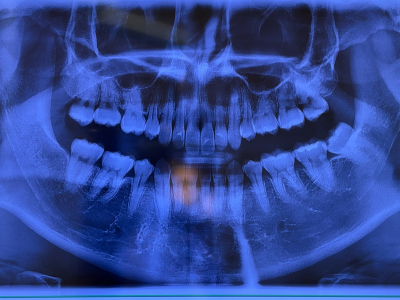

↓は撮ってきたレントゲン!歯並びは矯正済み!

無事、虫歯はゼロ🙆♂️